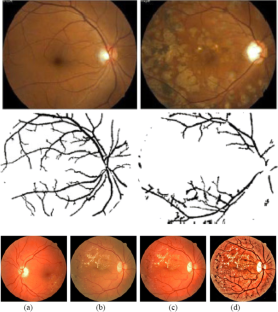

Fig. 1

Fig. 2

Fig. 3

Fig. 4